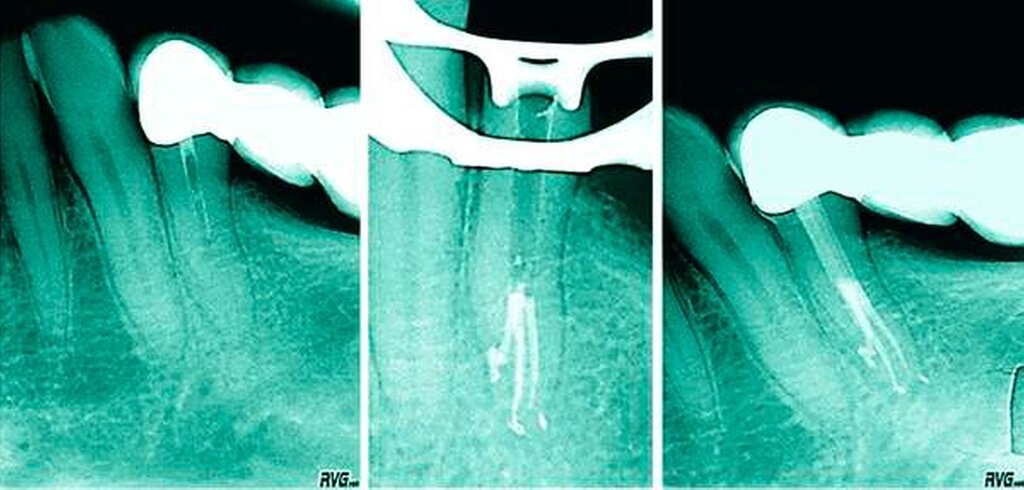

In einer Übersichtsarbeit, die acht Studien über die Anatomie von ersten Unterkiefer-Prämolaren zusammenfasst, ergab sich eine Prävalenz von mehr als einem Kanal in 24,2 Prozent aller Fälle [Cleghorn et al., 2007a]. Dabei überwiegen die zweikanaligen Prämolaren, die Prävalenz von drei Kanälen liegt bei unter 1 Prozent [Bürklein et al., 2017] (Abbildungen 4 und 5). Bei den zweikanaligen Zähnen zeigt sich üblicherweise ein weitlumiger Kanal von koronal nach apikal, von dem im mittleren oder im apikalen Drittel ein kleinerer lingualer Anteil abzweigt. Dieses Phänomen kann sehr ausgeprägt sein und macht die Behandlung extrem schwer (Abbildung 6).

Wie eingangs erwähnt sind die lingualen Kanalabzweigungen im mittleren und im apikalen Drittel nicht durch „Lesen“ des Dentins am Kavumboden zu erkennen. Diese Abzweigung ist nicht selten fast waagerecht und initial meist nur mit vorgebogenen Instrumenten ertastbar (Abbildung 11). Hier bieten sich kleine Stahlinstrumente der Größen 08 und 10 sowie Endodontie-Sonden mit Handgriff an (zum Beispiel Microopener der Firma Dentsply Sirona). Oft lassen sich solche Aufzweigungen erst nach sonoabrasiver Bearbeitung der lingualen Kanalwand finden und können dann gezielt präpariert werden. Der Zugang und die Instrumentierung der lingualen Abzweigung gestalten sich aufgrund der in Abbildung 11 gezeigten Winkel sehr schwierig – man sollte einen sehr guten Zugang zum lingualen Kanalanteil präparieren, um den Apex sicher erreichen zu können.